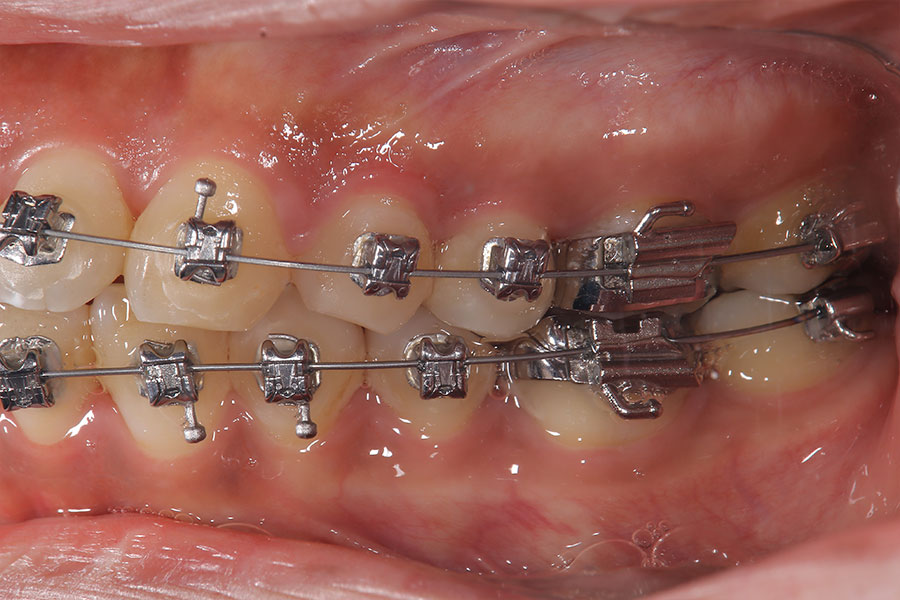

Before -側面-

After -側面-

| 施術内容 | ワイヤー矯正から、目立ちにくくメタルフリーなインビザラインへ変更しました。 金属アレルギーの不安が軽くなり、取り外しできることで清掃性も向上。見た目も自然で、治療中のストレスが少ない矯正方法です。 |

|---|---|

| 治療期間 | 2年間 |

| 費用 | インビザラインフル 767,800円 リテーナー 30,000円 |

| リスク・副作用 | 治療にともない、歯の破折や歯質の削合、場合によっては抜歯が必要となることがあります。また、金属や補綴物を除去する際に、完全に除去できない場合もあります。 |